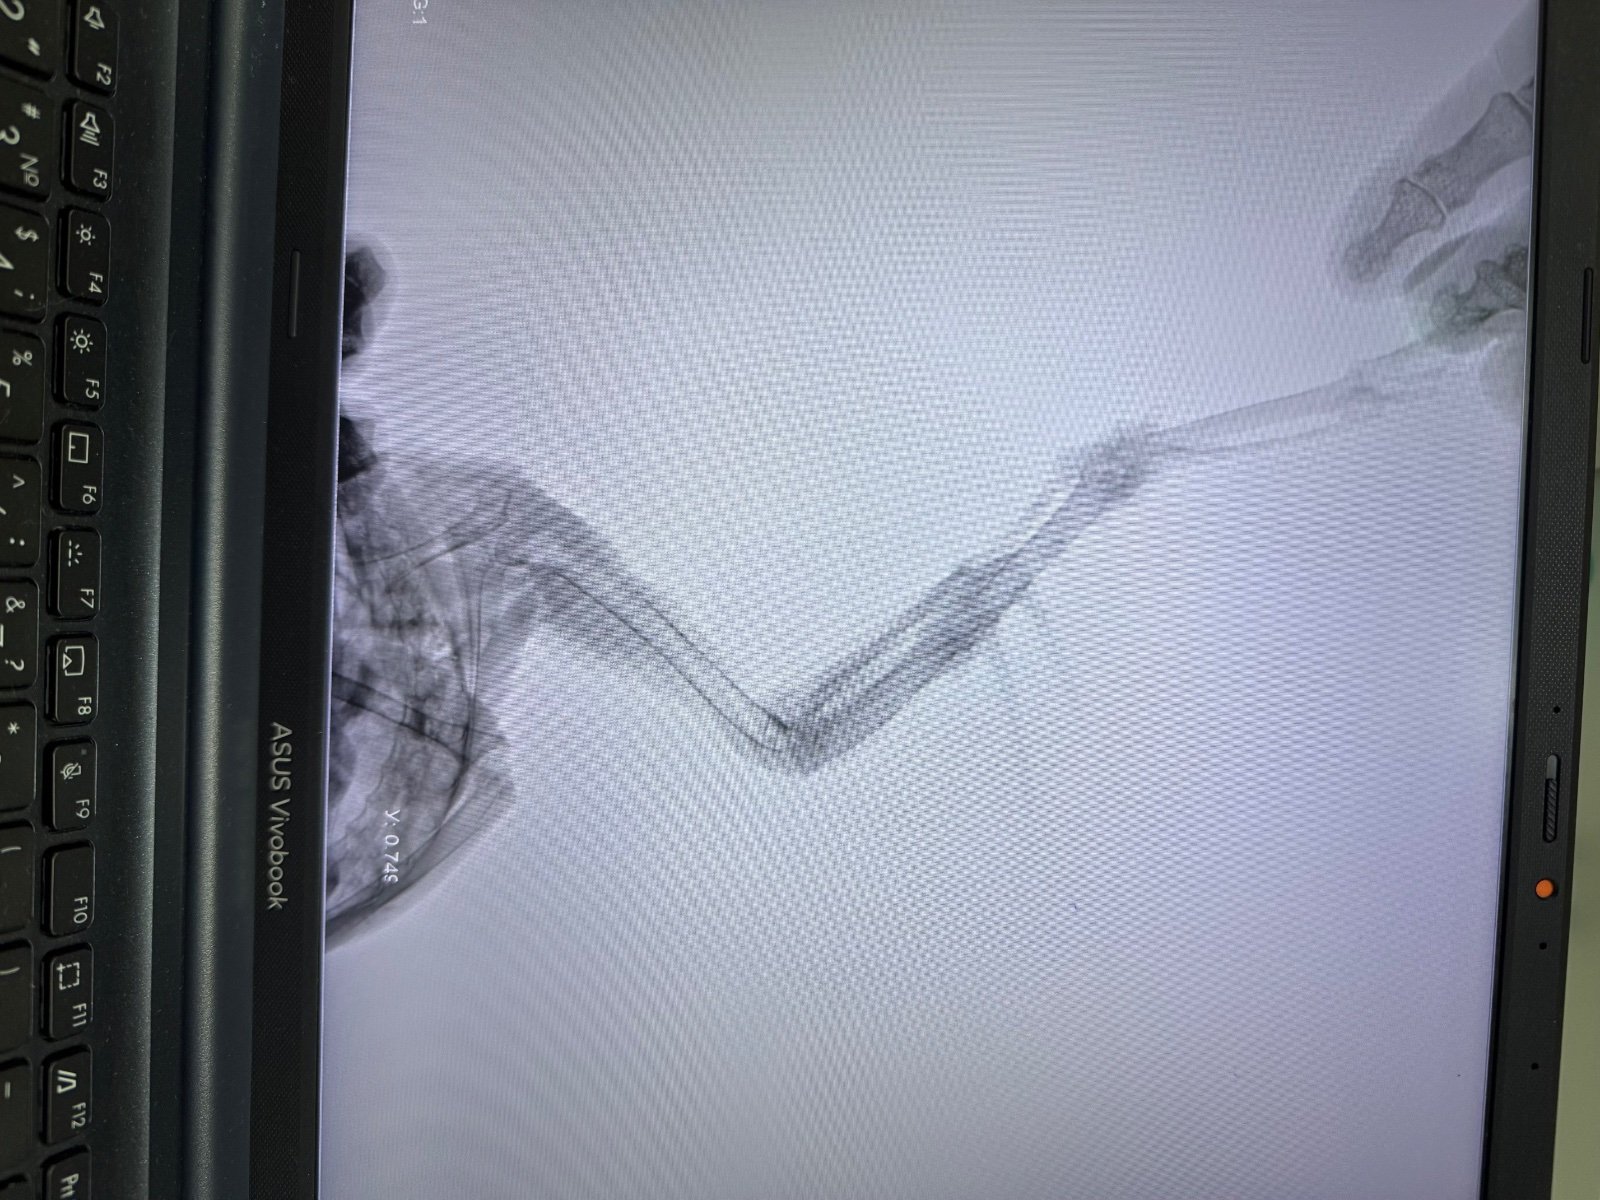

Здравствуйте! Подобрала молодого грача возле дома со сломанным крылом. В небольшом городе за лечение взялся лишь один ветеринар. Прооперировали 2 сентября опыта у меня нет, птицами никогда не интересовалась. После операции грачик хорошо питается (кормлю по гуглу - творог не жирный, мясо сырое, вареные куриные яйца; зофобас консервированный, гречка). Также даю минералы от зоомир общеукрепляющий. Активный, бесится, играется, танцует под гитару, но после операции меня немного побаивается, на руках больше не сидит как на первой фотографии. Сняли спицы 13 октября По поведению ничего не изменилось, кушает, пьет, бесится, по балкону до потолка взлетает. Но меня очень пугает, что крыло все еще висит и трясется. Последний рентген 23 октября Пожалуйста подскажите, что я могу сделать чтобы улучшить состояние крыла? Все ли хорошо по снимкам рентгена? Когда он начнет складывать крыло? Что я делаю не так? Из лечения никаких лекарств нам не назначали, только мумие. Я бы очень хотела оставить милашку у себя, но он уже бьется в окно, на улицу. Плюс мое место работы не позволяет заводить птиц, тк уезжаю на смену в другой город и не могу катать его с собой постоянно. Очень хотелось бы отпустить его к своим.